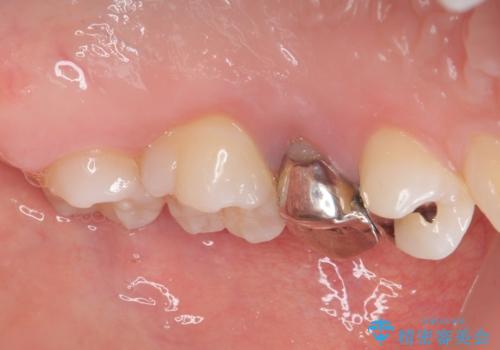

- 笑った時に目立つ銀歯を治したいとのことで来院された患者様です。検査の結果、オールセラミッククラウンによる補綴治療を行っていくことにしました。

拡大鏡視野下で銀歯を外し、オールセラミッククラウンに適した形に整えました。